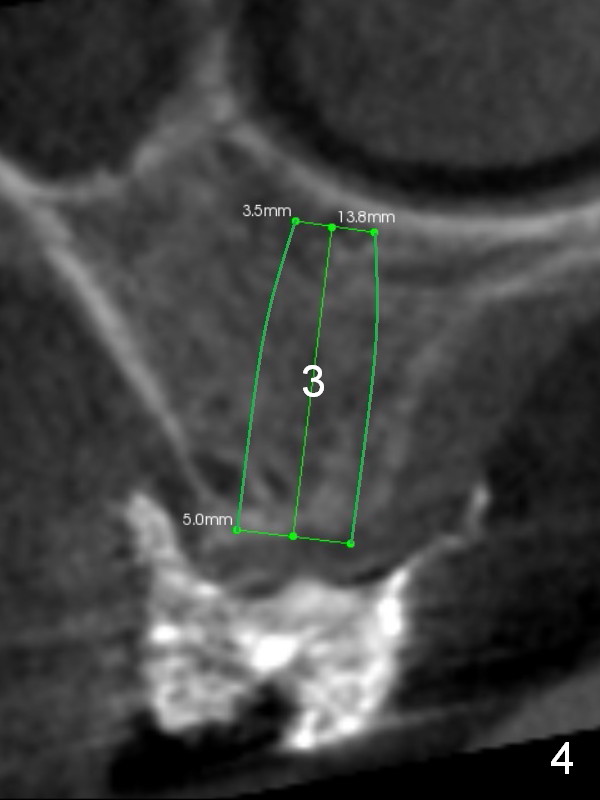

The ridge of the upper right posterior region is variable: narrow at the sites of #4 and 5 (Fig.2,3) and wide at #2 and 3 (Fig.4,5). One-piece implants are going to be placed at the premolars, while wide and extra wide implants at the molars.